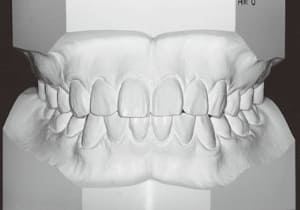

26 After Retention 7-8-’96

31 After Retention 7-8-’96

The facial type changed from backward divergent to straight between the initial visit and after retention (27–31). Cephalometric X-rays reveal significant mandibular growth (32).

Treatment period from initiation to completion of active treatment lasted 6 years and 2 months, with appliances worn for 3 years and 8 months of that time. Retention lasted 2 years and 2 months following active treatment.